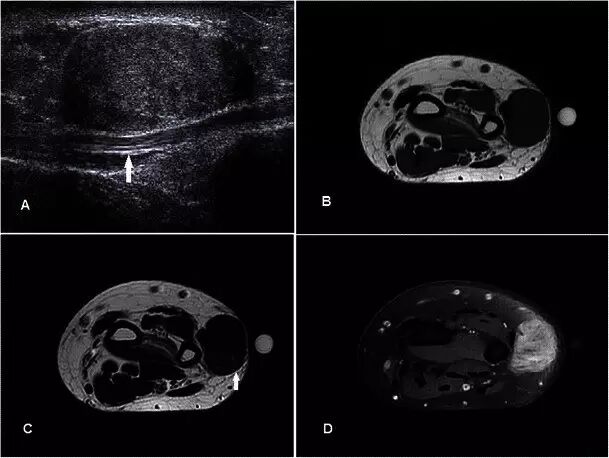

腱鞘巨细胞瘤Giant cell tumour of tendon sheath GCTTS是常见的肿瘤,通常在30-50岁时表现为无痛的肿块,具有轻微的女性偏好。 它们通常存在于与退行性关节相关的手或脚中,并且被认为是对邻近炎症的反应性损伤而不是真正的肿瘤[40]。 GCTTS在组织学上是良性的,但是在10-20%的病例中,在平片上可以看到相邻骨的压力变化[41](图13a)。MR显示与关节和腱紧密相关的损伤,主要是T1w序列上的低信号和T2w序列上的中等至稍高的信号(图13b-e)。 GRE序列上可见典型的异常图像,因为血铁素沉积,这是一个有用的特点[42]。 由于在胶原基质中存在许多增殖性毛细血管,观察到强的增强。 鉴别诊断包括局灶性结节性滑膜炎,其还含有铁氧化物,而更加异质的信号和增强可导致与软组织肉瘤的混淆。

图13.GCTTS在一名23岁的女性,有1年的右拇指肿胀和轻度疼痛的病史。 (a)平片显示在第一掌骨(箭头)的头部的明确的透亮区。 (b)T1w序列显示包围屈肌腱长肌的中间信号的分叶皮下病变(箭头)。 (c)病灶在T2w-FS序列上显示不均匀高信号。 在下面的骨头上有压力侵蚀。 (d)在GRE序列(箭头)上证明了易感性的Foci。 (e)有积极和相当均匀的增强